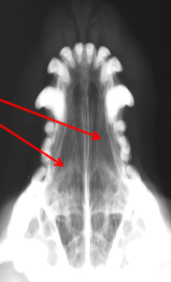

ID Radiographic View

Open Mouth VD view of Nasal Cavity

ID

Ethmoid Turbinates

Maxillary Turbinates

VOmer Bone

Palantine Foramen